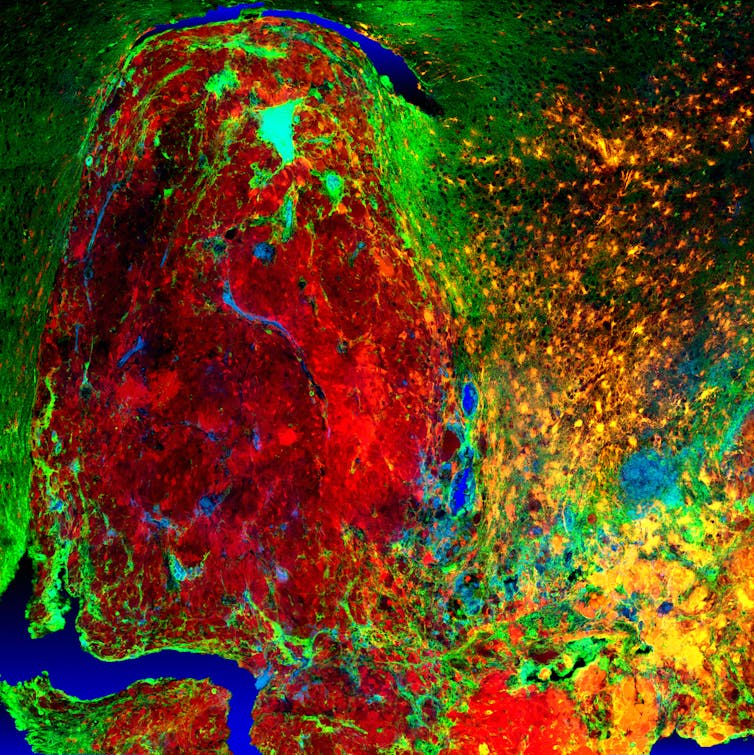

Understanding the characteristics of high-grade brain tumours is crucial to finding treatments for disease. High-resolution fluorescent imaging allows us to investigate how the normal brain cells become cancer cells and how they behave. This image demonstrates the infiltration process of the cancer cells (red) into the normal brain tissue (green).